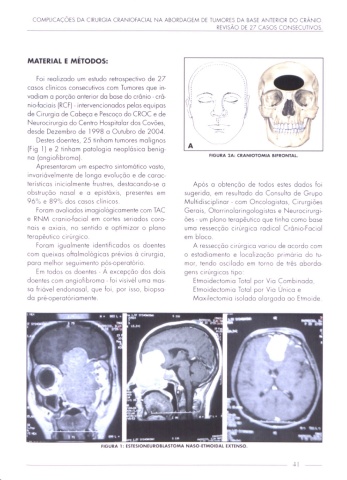

no (ongiohbromo). "GUIA 2A: CIANIOTOMIA Bl'IONTAL

HGURA l: ESTESIONEUIOILASTOMA NASO-UMOIDAL EXTINSO.